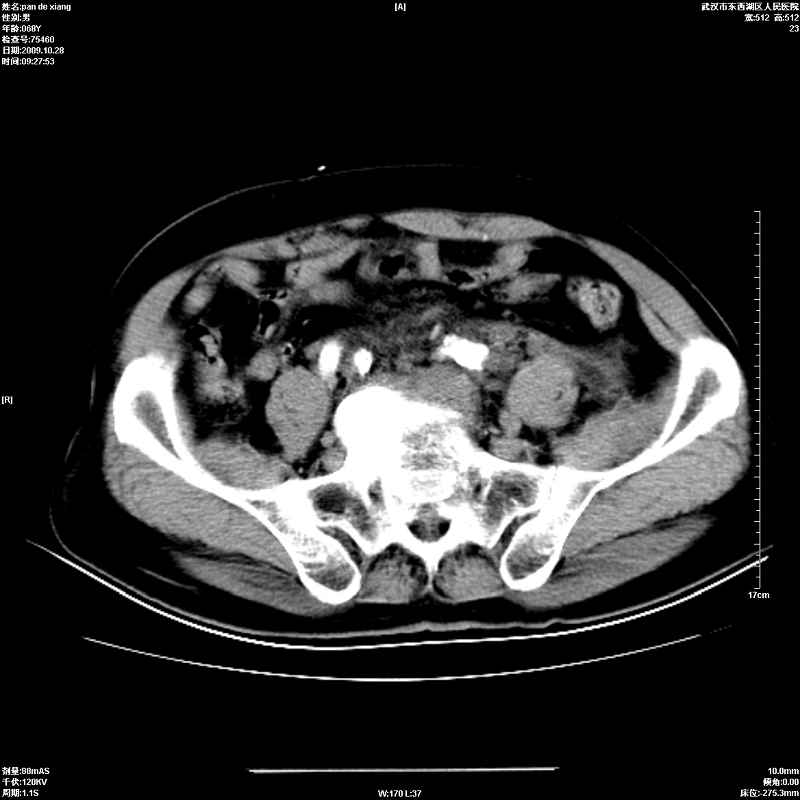

以下是引用杀毒软件在2009-10-28 20:41:00的发言:[br]结合临床考虑---白血病双肾改变或淋巴瘤。

以下是引用zxl51642在2009-10-29 9:59:00的发言:[br]结合临床“单克隆免疫球蛋白血症”,考虑双肾为继发损害并肾功能不全(尿中大量igg及少量iga、igm等大分子免疫球蛋白滤出所致继发损害),椎前软组织肿块为髓外造血。与浆细胞瘤有区别,平扫时有战友说的很清楚。